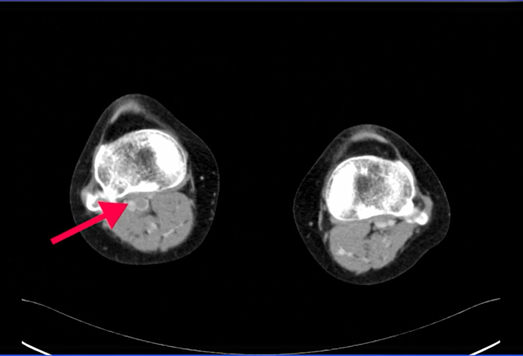

続いて静脈相で静脈血栓を確認する。

膝窩静脈内に血栓あり。